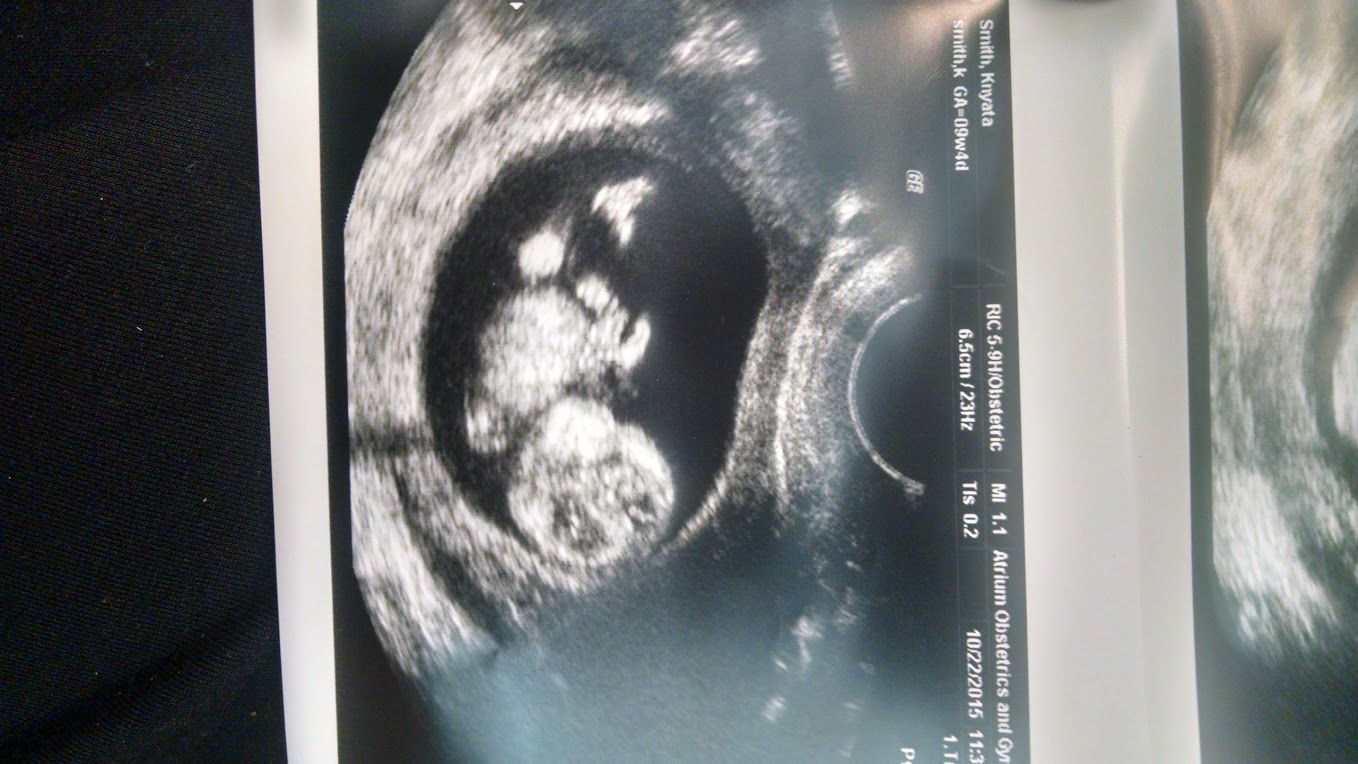

We had our first ultrasound yesterday, baby is measuring right on track for a due date of 5/18. I'm 10 weeks today. Strong heart beat too! Loved seeing our sweet, little one for the first time!

Had our first U/S yesterday.... Heartbeat is 167. Technician said she can't tell me anything else though. Radiologist will look at the pictures and send them to my doc who will give me details....so now I wait until November 2 to find out due date and everything..

Just had my first US. I have been convinced I am further along than 12 weeks. I ovulate early with a short cycle. Found out I am a full week further along! 13w4d which puts me at April 24th EDD. 144 hb and the US tech kept reassuring me that even though I won't get official results for a week that baby has a very thin measurement for the NT.